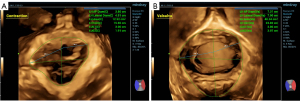

Transperineal 3D ultrasonography was performed and the static images were saved. The abdominal volume probe was used to start 3D mode on the midsagittal plane of the pelvic floor, and the 3D volume images were collected after anal contraction and Valsalva maneuver. The transverse LH images of the LH were obtained, and the 3D scanning mode was started to obtain the volume data of the pelvic floor and display the axial plane image. The tomographic ultrasound image (TUI) was used to observe the continuity of the LAM and the morphology of the LH. Taking the anteroposterior diameter of the minimum LH as the reference line, 5 mm below the reference line to 12.5 mm above the reference line, and the number of layers in the fracture section as 9, multiple parallel sections of the LH images could be obtained. The standard requires that the pubic symphysis shown in images 3–5 must present open, closed, and closed states, respectively (7). LAM fracture showed discontinuity or even no display in at least three levels, to determine the depth of the defect and measure the maximum width of the defect, and to further verify the LAM damage found in 2D mode (Figure 3).

In contrast to the traditional 2D ultrasound method of directly observing LAM shape and attachment point continuity, the diagnosis method of LAM was first proposed by Dietz in 2005 (23). LAM injury was diagnosed by TUI mode under 3D conditions on the volume obtained during maximum contraction of the pelvic floor muscles. LAM avulsion was diagnosed when LAM discontinuity was present in at least three consecutive sections in TUI mode between the insertion of the puborectalis muscle and the attachment of the pubic ramus. Through the TUI pattern, it is possible to observe whether the LH is symmetrical or not, and it is also reasonable to infer LAM injury when both sides of the LH are asymmetrical (24). In most cases of LAM injury, qualitative evaluation can diagnose the presence or absence of LAM injury. However, in some cases, subjective perception alone is not sufficient to be comprehensive. Using TUI, LAM injury can be quantitatively assessed through two key metrics: (I) symmetry evaluation of the LH across sequential planes, and (II) measurement of the LUG, defined as the distance between the urethral center and the LAM insertion point on the pubic ramus. LAM avulsion was diagnosed when LUG exceeded 25 mm in three consecutive TUI planes. Due to the different pelvic sizes of women of different races, some studies have shown that the best LUG cut-off values for the diagnosis of LAM injury in Asian women are 23.65 and 23.05 mm (25). This study showed that the LUG of the forceps group, the non-forceps group, and the elective cesarean section group decreased in turn in the state of anal contraction. The LHA of vaginal delivery (with and without forceps) by Valsalva was greater than that of elective cesarean section, which was consistent with the results of the above study, and showed that forceps had some effect on LAM injury.